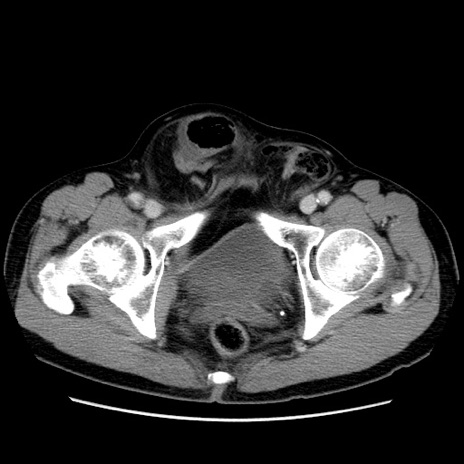

症例34(横断像)

【症例】60歳代 男性

【主訴】右鼠径部膨隆

【現病歴】1年程前より右鼠径部膨隆あり。自己にて還納可能だったため放置していた。3時間前より右鼠径部の脱出を認め、還納困難となり受診。

【既往歴】高血圧

【身体所見】右鼠径部に小児頭大の膨隆あり。弾性硬であり、用手還納は困難。左鼠径部にも膨隆を認める。脱出はなし。

【データ】WBC 15500、CRP 測定なし